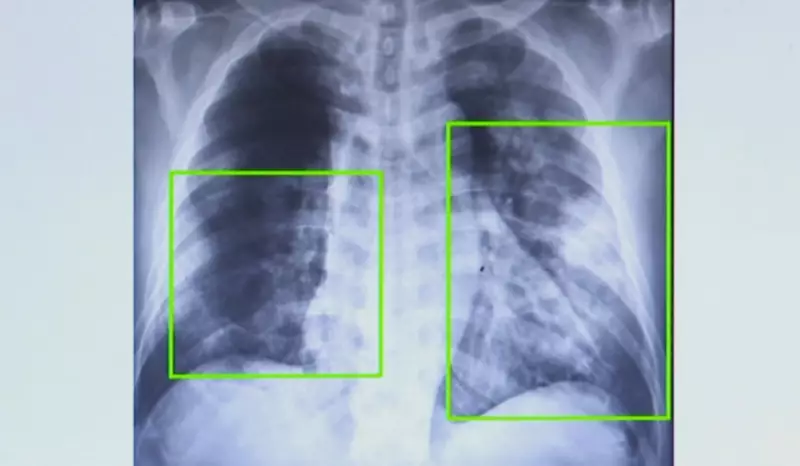

Os casos de pneumonia apresentaram um crescimento alarmante em todo o estado de São Paulo, com destaque para a região de Campinas, onde o número de atendimentos praticamente duplicou nos últimos sete meses. Os hospitais e unidades de saúde enfrentam superlotação devido ao aumento significativo de pacientes com a doença.

De janeiro a agosto deste ano, a Secretaria Estadual da Saúde registrou 202.357 atendimentos por pneumonia em todo o estado. Este número representa um aumento de 20% em comparação com o mesmo período do ano passado, quando foram contabilizados 167.263 casos.

Na região de Campinas, a situação é ainda mais crítica: os atendimentos por pneumonia quase dobraram em apenas sete meses, conforme dados divulgados nesta sexta-feira (21).